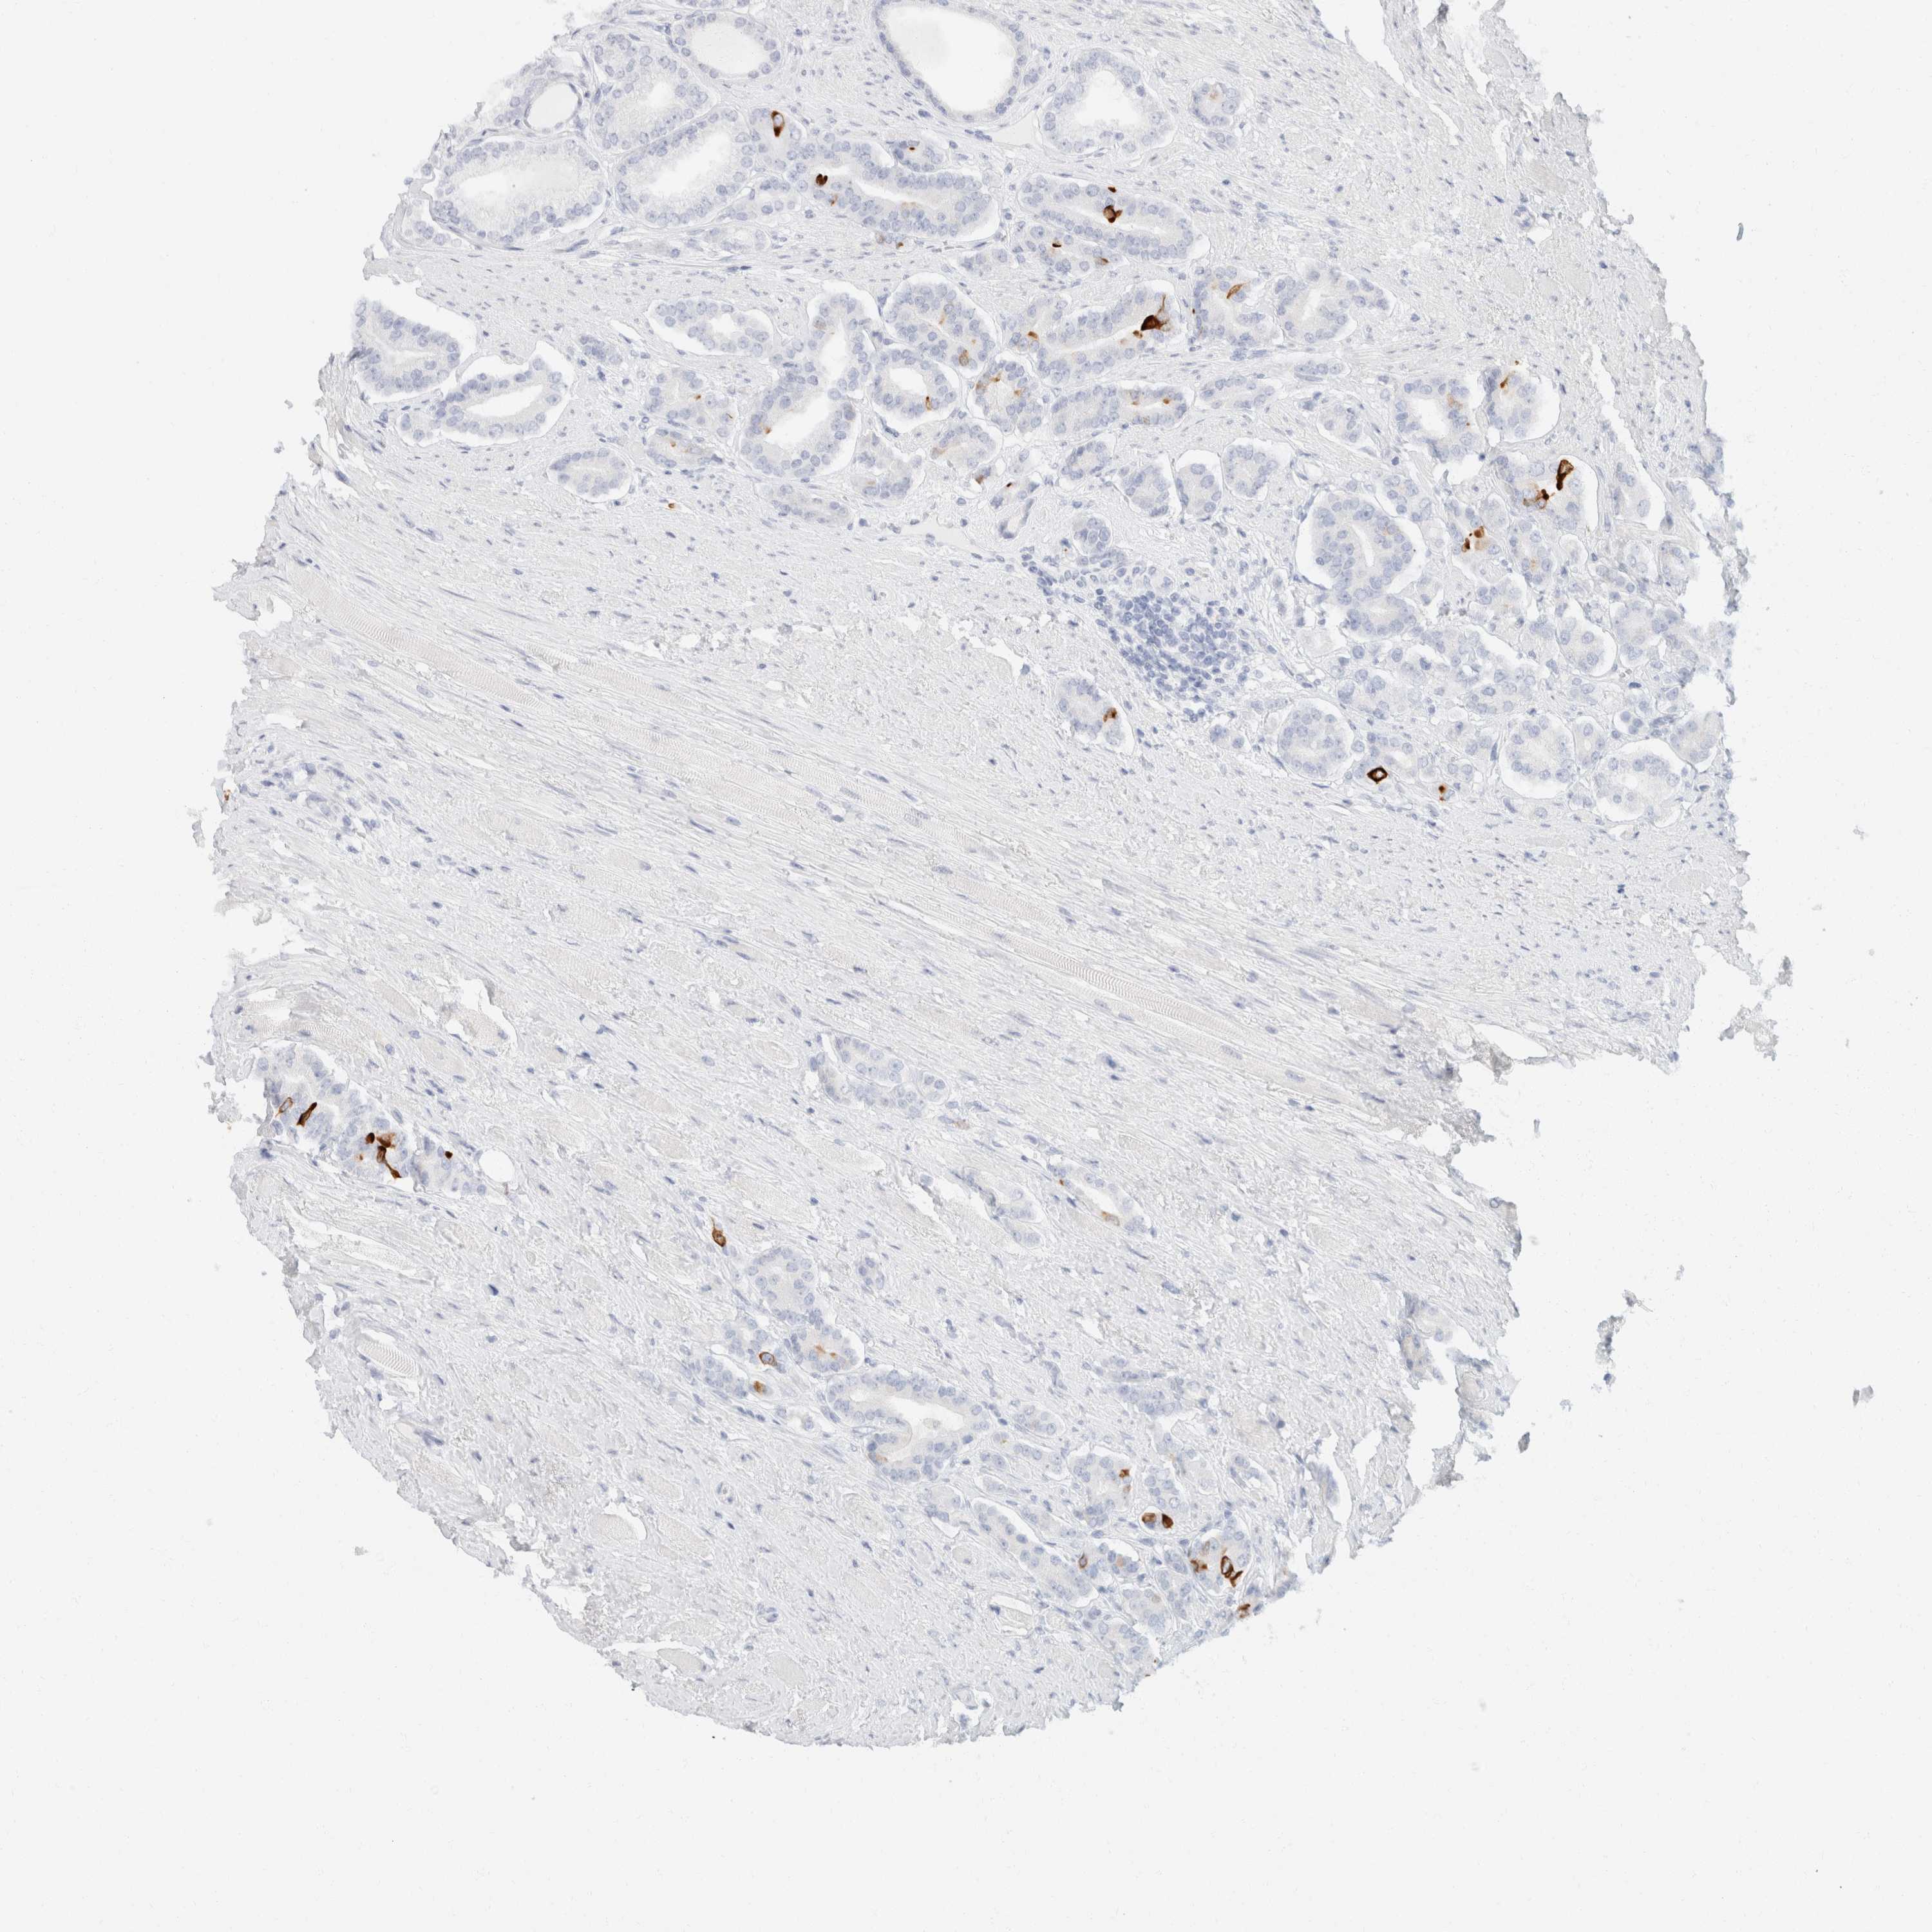

PROSTATE CANCER - Protein expressioni

A mouse-over function shows sample information and annotation data. Click on an image to view it in a full screen mode. Samples can be filtered based on level of antibody staining by selecting one or several of the following categories: high, medium, low and not detected. The assay and annotation is described here.

Note that samples used for immunohistochemistry by the Human Protein Atlas do not correspond to samples in the TCGA dataset.

Antibody stainingi

Antibody staining in the annotated cell types in the current human tissue is reported as not detected, low, medium, or high, based on conventional immunohistochemistry profiling in selected tissues. This score is based on the combination of the staining intensity and fraction of stained cells.

Each image is clickable and will lead to virtual microscopy that enables deeper exploration of all samples and also displays staining intensity scores, fraction scores and subcellular localization as well as patient and tissue information for each sample.

Antibody HPA024309

Antibody HPA024684

Antibody HPA027236

Antibody CAB000032

Staining

High

Medium

Low

Not detected

Intensity

Strong

Moderate

Weak

Negative

Quantity

>75%

75%-25%

<25%

None

Location

Nuclear

Cytoplasmic/membranous

Cytoplasmic/membranous,nuclear

Adenocarcinoma, High grade

Adenocarcinoma, Low grade

Adenocarcinoma, Medium grade